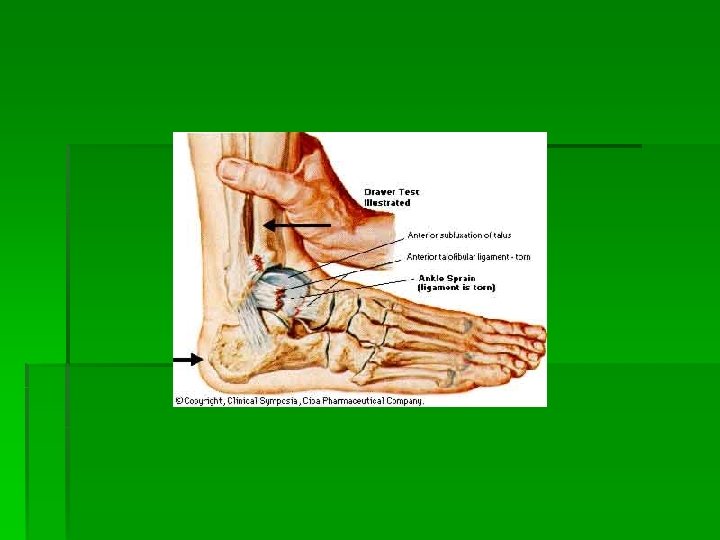

85% of all ankle sprains involve some plantar flexion of the ankle and inversion of the foot. The remaining 15% consist of eversion mechanisms which are often the result of an outside force such as being fallen on from the outside.

The syndesmosis ligament is often also injured with an eversion force. If the tibia and fibula spread on the talus, the ankle mortise is disrupted and the ankle can become very unstable. It is also not unusual to see an associated fibula fracture with an eversion mechanism. (see x-rays below) Assessment of a syndesmosis sprain will be difficult for the initial 24 to 48 hours. If the ankle is quite swollen and edematous assessment of a syndesmosis sprain may be difficult until the pain and swelling have isolated to individual areas or x-rays show some spreading of the ankle mortise.